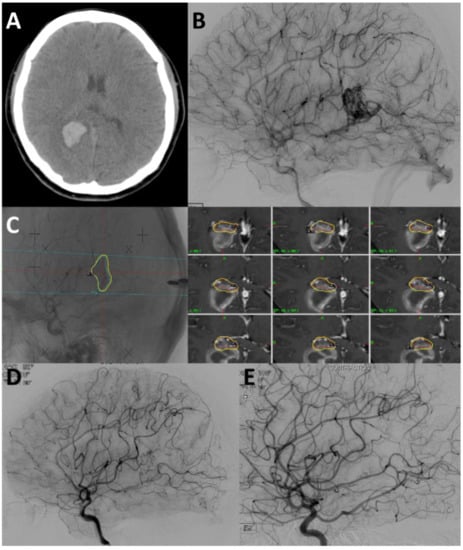

4.1. Case 1